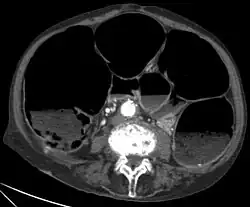

CT-Scan showing a Cross-section of the abdomen of an elderly lady with an IPO.X-rays – may show intestinal air fluid levels (seen with true mechanical intestinal obstruction)